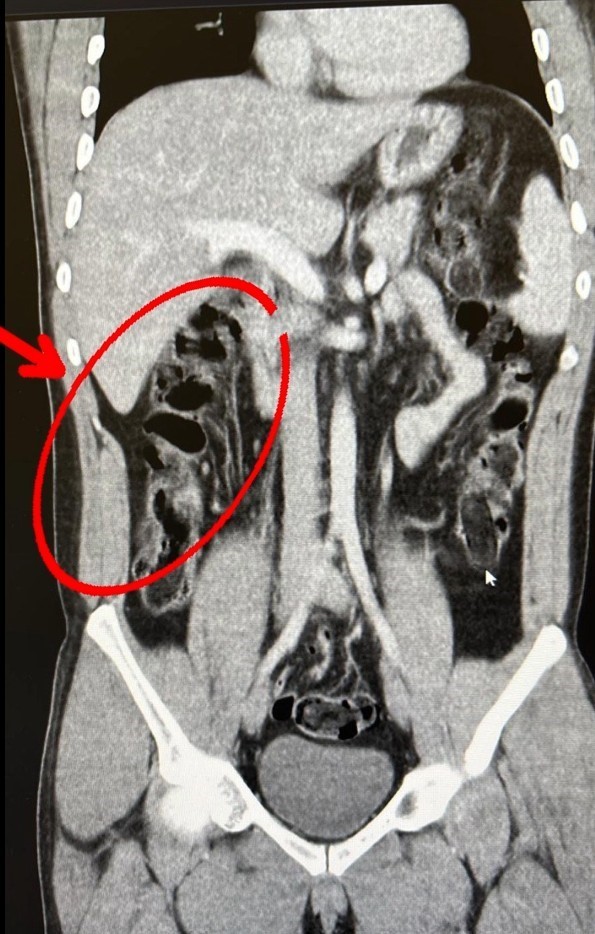

S.S. ve F.M.K. isimli şahısların hastanede yapılan iç beden muayenesi sonucunda 35 kapsül halinde toplam 278 gram eroin maddesi ele geçirildi. Şüphelilerin havalimanındaki görüntüleri, yakalandıktan sonra muayene edilme anları ve yuttukları kapsüllerin yer aldığı film sonu

çları kameralara yansıdı. 2 şüpheli, "uyuşturucu veya uyarıcı madde ticareti yapmak ve sağlamak" suçundan adli makamlarca tutuklandı.